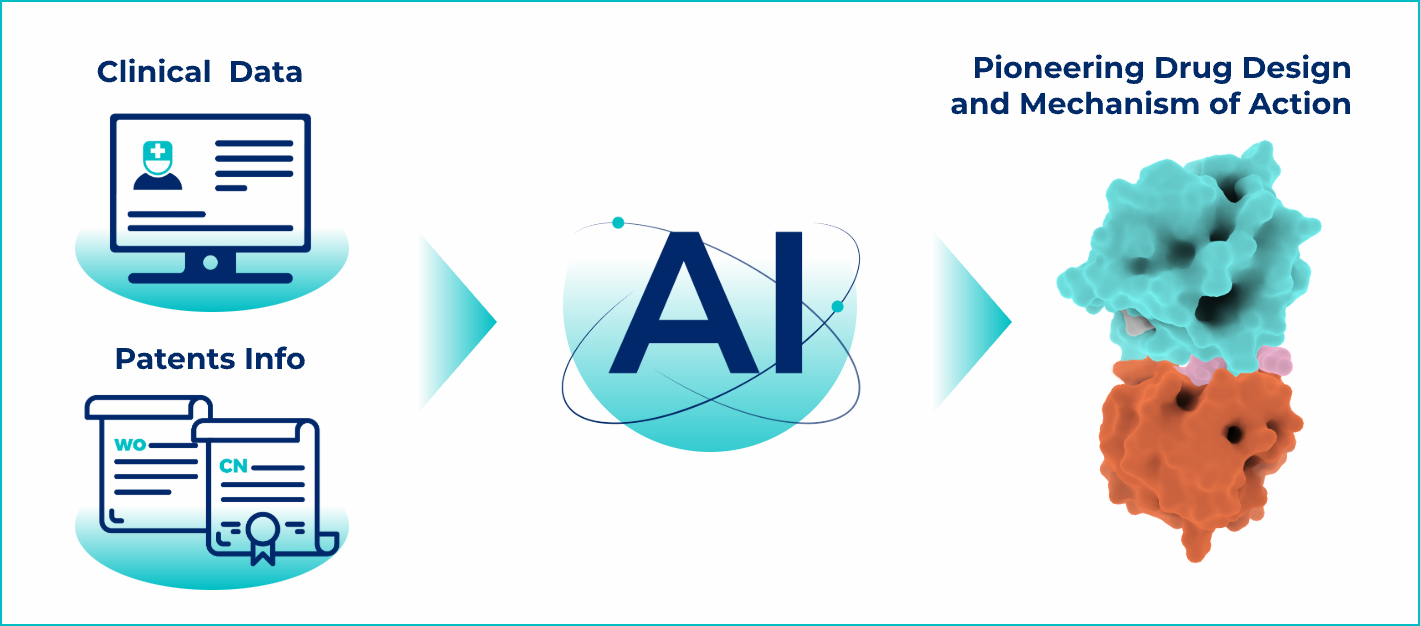

Literature & Patent Analysis

We provide a comprehensive review of

research backgrounds, biological functions, and the

entire R&D history of

related drugs. Our system also collates

and interprets

compound patents,

offering insights for Best-in-Class (BIC)

or First-in-Class (FIC)

development

strategies.

Structure &

Molecular Design

We model target-drug binding,

analyze structure-activity relationships,

and propose new molecular designs.

Our AI evaluates and screens potential

molecules to maximize your chances of

success

in lab validation.

Clinical Analysis

We analyze the success and failure of drugs in clinical trials to help you refine

your development strategy.